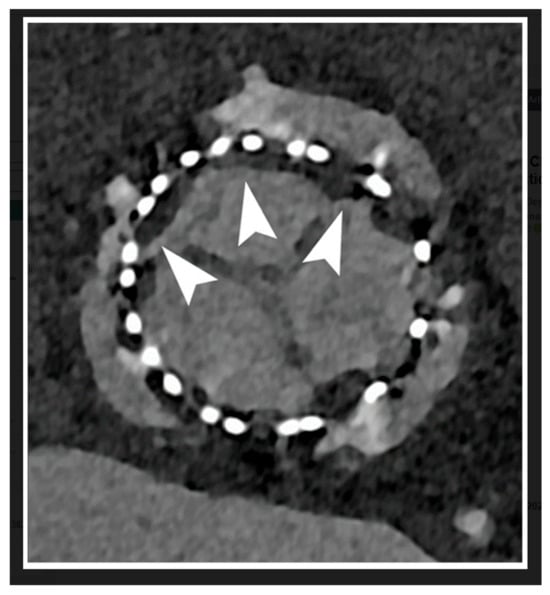

- Park, M.J.; Jung, J.I.; Choi, Y.-S.; Ann, S.H.; Youn, H.-J.; Jeon, G.N.; Choi, H.C. Coronary CT angiography in patients with high calcium score: Evaluation of plaque characteristics and diagnostic accuracy. Int. J. Cardiovasc. Imaging 2011, 27, 43–51. [Google Scholar] [CrossRef] [PubMed]

- Vavere, A.L.; Arbab-Zadeh, A.; Rochitte, C.E.; Dewey, M.; Niinuma, H.; Gottlieb, I.; Clouse, M.E.; Bush, D.E.; Hoe, J.W.; de Roos, A.; et al. Coronary artery stenoses: Accuracy of 64-detector row CT angiography in segments with mild, moderate, or severe calcification—A subanalysis of the CORE-64 trial. Radiology 2011, 261, 100–108. [Google Scholar] [CrossRef]

- Chen, C.-C.; Chen, C.-C.; Hsieh, I.C.; Liu, Y.-C.; Liu, C.-Y.; Chan, T.; Wen, M.-S.; Wan, Y.-L. The effect of calcium score on the diagnostic accuracy of coronary computed tomography angiography. Int. J. Cardiovasc. Imaging 2011, 27, 37–42. [Google Scholar] [CrossRef] [PubMed]

- Meng, L.; Cui, L.; Cheng, Y.; Wu, X.; Tang, Y.; Wang, Y.; Xu, F. Effect of heart rate and coronary calcification on the diagnostic accuracy of the dual-source CT coronary angiography in patients with suspected coronary artery disease. Korean J. Radiol. 2009, 10, 347–354. [Google Scholar] [CrossRef][Green Version]

- Meijs, M.F.L.; Meijboom, W.B.; Prokop, M.; Mollet, N.R.; van Mieghem, C.A.G.; Doevendans, P.A.; de Feyter, P.J.; Cramer, M.J. Is there a role for CT coronary angiography in patients with symptomatic angina? Effect of coronary calcium score on identification of stenosis. Int. J. Cardiovasc. Imaging 2009, 25, 847–854. [Google Scholar] [CrossRef][Green Version]

- Sun, Z.; Ng, C.K. High calcium scores in coronary CT angiography: Effects of image post-processing on visualization and measurement of coronary lumen diameter. J. Med. Imaging Health Inform. 2015, 5, 110–116. [Google Scholar] [CrossRef]

- Sun, Z.; Ng, C.K.C.; Xu, L.; Fan, Z.; Lei, J. Coronary CT Angiography in Heavily Calcified Coronary Arteries: Improvement of Coronary Lumen Visualization and Coronary Stenosis Assessment with Image Postprocessing Methods. Medicine 2015, 94, e2148. [Google Scholar] [CrossRef] [PubMed]